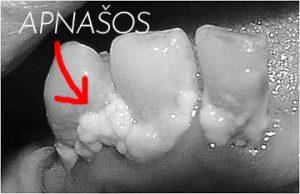

Apnašos - viena dantenų uždegimo priežasčių!Kadangi minkštos apnašos yra viena pagrindinių dantenų uždegimo priežasčių, būtina apie jas žinoti daugiau. Jos susideda iš daugybės įvairių komponentų: epitelio ląstelių, leukocitų, mikrofagų, vandens, seilių baltymų. Vis dėlto, daugiausiai jų atsiradimui įtakos turi mikroorganizmai. Kol vyksta formavimosi procesas, jas sunku aptikti. Būtent todėl patariama naudoti specialius skysčius ar tabletes, kurios leis pamatyti apnašas. Jei minkštosios apnašos nėra tinkamai bei laiku pašalintos, prasideda mineralizacija – jos pavirsta į dantų akmenis. Paprastai šis procesas įvyksta per 20 dienų laikotarpį, o tiksliai jo trukmei įtakos turi įvairūs veiksniai, įskaitant ir geriamojo vandens sudėtį.